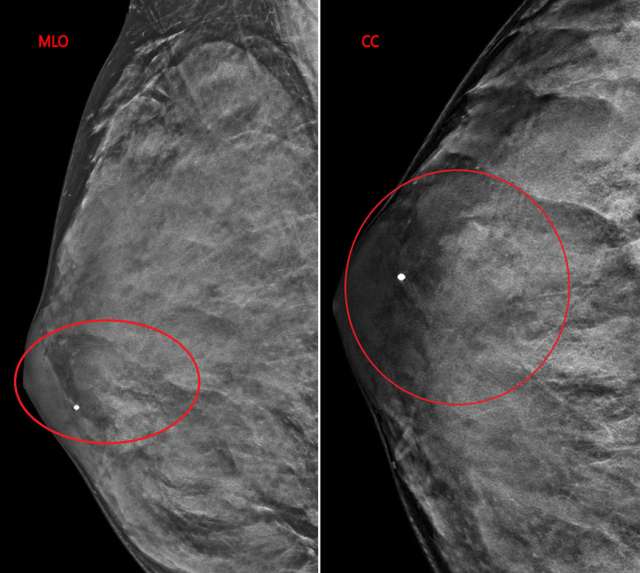

The patient underwent a diagnostic mammogram which revealed extremely dense breasts and an oval mass with circumscribed and obscured margins seen in the right breast at 9 o’clock at anterior depth (Figure 1). Targeted sonographic images were subsequently obtained which revealed a hypoechoic vascular oval mass with circumscribed margins measuring 24 x 10 x 34 mm seen in the right breast at 9 o'clock located 3 centimeters from the nipple (Figure 2). Given the patient’s medical history these findings were given BIRADS-4A and an ultrasound biopsy was recommended.

Case Female Transgender Figure 1

Figure 1: MLO and CC views of the right breast, demonstrate an oval mass with circumscribed and obscured margins at 9 o’clock at anterior depth denoted by red circle.